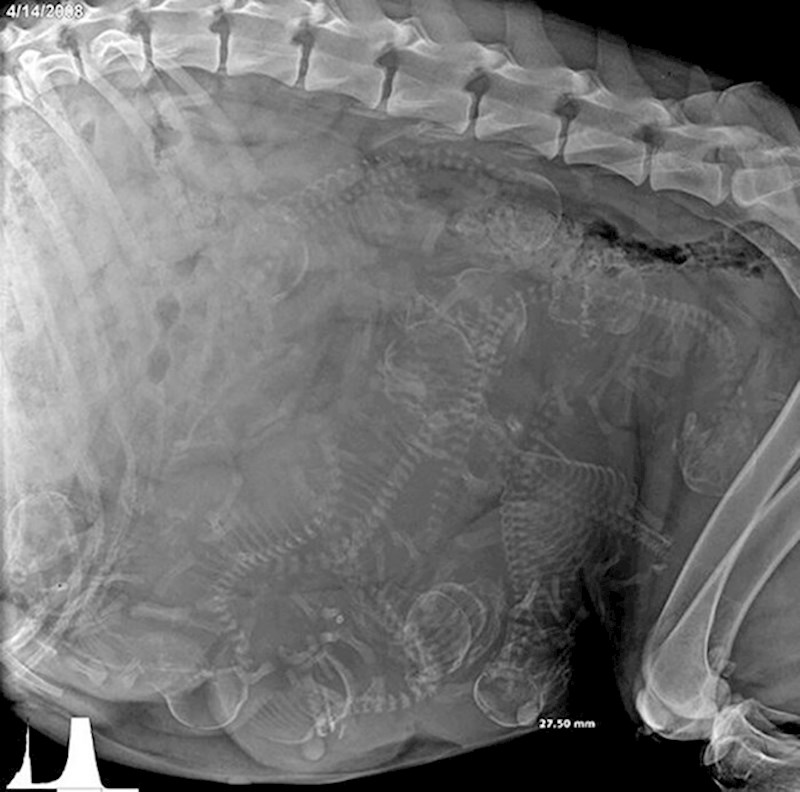

13. Rendgenska snimka trudnog psa